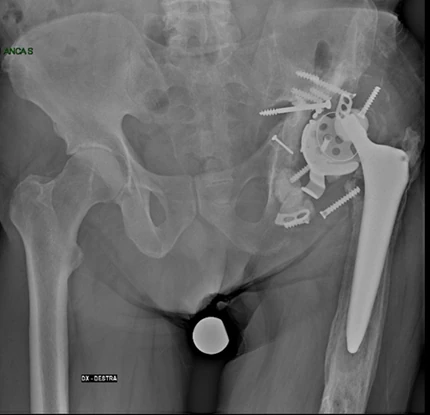

A tale proposito ho sviluppato in collaborazione con Medacta, nota e azienda Svizzera molto attiva in campo ortopedico e aperta alle innovazioni tecnologiche, un nuovo impianto specifico per la chirurgia di revisione acetabolare progettato per affrontare i casi più complessi di difetto osseo sfruttando per la stabilità meccanica l’osso iliaco.

Caratteristiche distintive del cotile Mpact Ilac Screw e perché viene scelto in casi difficili:

1. Design e Modularità

È un sistema non cementato che punta sulla stabilità meccanica immediata e sulla rigenerazione biologica a lungo termine:

- Forma emisferica: consente la correzione di inclinazione ed antiversione

- Vite Polare: è l’innovazione tecnologica peculiare che consente di massimizzare la stabilità primaria ancorandosi saldamente entro l’osso iliaco solitamente presente anche nei casi più gravi di difetto osseo.

2. Indicazioni Specifiche

Il Cotile Mpact Ilac Screw viene impiegato quando il normale “alloggio” dell’anca è compromesso da:

- Mobilizzazione della vecchia protesi che ha “scavato” o distrutto parte del bacino.

- Difetti ossei gravi (classificati come Paprosky II o III) e disgiunzione pelvica

- Esiti di traumi complessi o displasie congenite che alterano l’anatomia standard.

3. Stabilità iliaca

- Concetto vecchio, disegno moderna: La vite iliaca funge da vero e proprio “pilastro”, trasferendo il carico meccanico direttamente nella colonna posteriore/superiore del bacino, entro l’osso iliaco, bypassando le zone di osteolisi e il difetto cavitario/segmentario dell’acetabolo.

In sintesi, il cotile Mpact Ilac Screw è un cotile innovativo che permette di “ricostruire” l’articolazione anche in presenza di ampi difetti ossei evitando il ricorso a protesi custom-made o altri impianti molto più complessi e costosi.